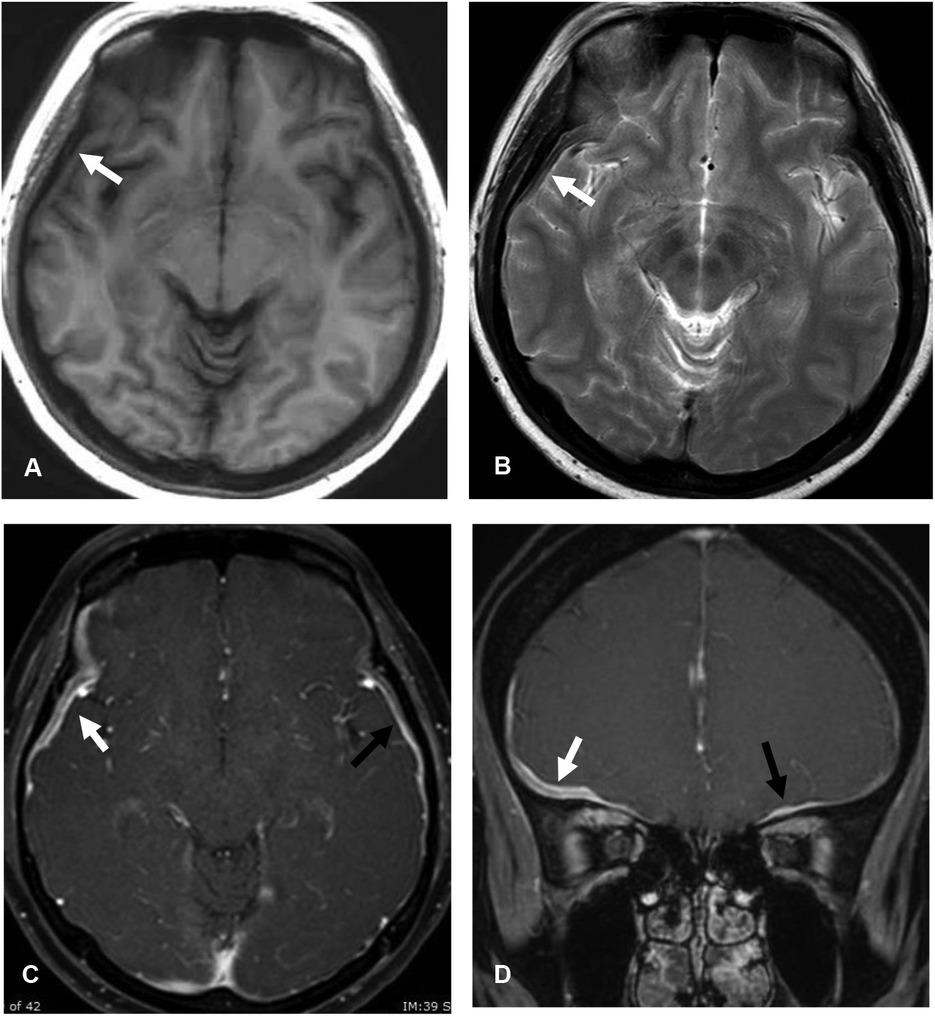

Three of 23 idiopathic HP patients (13%) showed central hyperintensity and dark intensity rim on T2WI, which was defined as T2-rim pattern (Figure 4). The T2-rim pattern was not found in secondary HP group. Details of MRI findings are in Table 4.

Figure 4

Idiopathic hypertrophic pachymeningitis (IHP) with T2-rim pattern. Axial T1-weighted image (A) and T2-weighted image (B) show T1 iso-intense and central T2 hyperintense with peripheral dark T2 intense (T2-rim pattern) of the thickened dura along right frontal and right temporal convexity (arrow). Axial (C) and coronal (D) gadolinium-enhanced T1-weighted images demonstrate rim enhancement (white arrows). Smooth and homogeneous enhanced thickened dura at left anterior cranial fossa (black arrows) is also observed.

Our study found T2 hypo-/dark intensity in majority of idiopathic HP (52%) and in minority of secondary HP (27%). However, our patients did not exhibit hypointensity with thin hyperintense edges on T2WIs as shown in prior studies [10, 11]. Interestingly, three idiopathic HP patients (13%) had thick hyperintense dura with hypointense rim on T2WIs (T2-rim pattern), which was described in the prior study [12]. None of secondary HP showed T2-rim pattern. This finding is promising to be MRI characteristics of idiopathic HP. Some of our patients (13%) showed diffuse T2 hyperintensity of the thickened dura. This finding was also described in the previous study and probably reflects vessels and inflammatory cells in the dural tissue [9, 10, 11]. There was no significant T2 intensity difference between idiopathic HP and secondary HP. Different signal intensity may represent different stages of disease with variable fibrosis, collagen, and inflammatory cells.

Majority of idiopathic HP showed homogeneous enhancement, which was well described in prior studies [9, 13, 14]. Prior studies showed enhancement of dural edges in idiopathic pachymeningitis [9, 10]. We found this enhancement pattern in two idiopathic HP and one secondary HP patients. Hypointense/dark SI on T2WIs with homogeneous enhancement pattern were found only in idiopathic HP and reached statistical significance (75% vs 0%, P = 0.044). These findings may raise possibility of idiopathic HP.